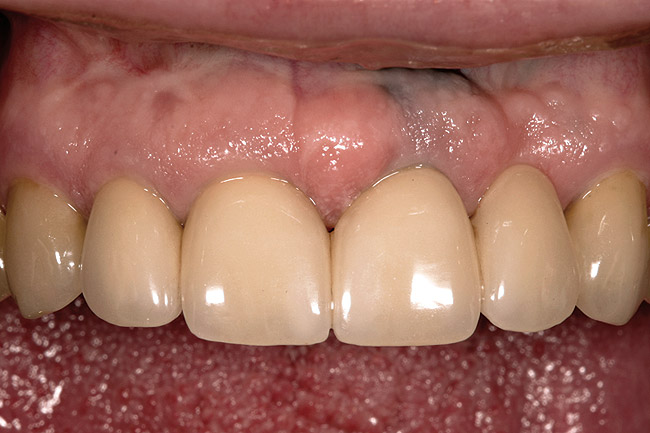

Figure 11  This is a 4-year recall photograph following placement of the final restorations.

Figure 11

Rule 3: If a sulcus greater than 2 mm is found on the facial, evaluate the teeth esthetically to see if a gingivectomy could be performed to lengthen the teeth and create a 1.5-mm sulcus. Then, treat using Rule 1 (Figure 6, Figure 7, Figure 8, Figure 9, Figure 10 and Figure 11).

The rationale for Rule 3 is that it is more difficult to place a margin one-half the depth of a deep sulcus as compared to 0.5 mm to 0.7 mm below tissue. In addition, the stability of the free gingival margin is less predictable with a deep sulcus than with a shallow sulcus. Therefore, if it is possible to perform a gingivectomy, lengthening the tooth and leaving a

1-mm to 1.5-mm sulcus, doing so will create a more predictable situation in which to place an intracrevicular margin. This does not, however, ensure that the tissue will remain at the level placed, because gingivectomies are frequently followed by some gingival rebound.